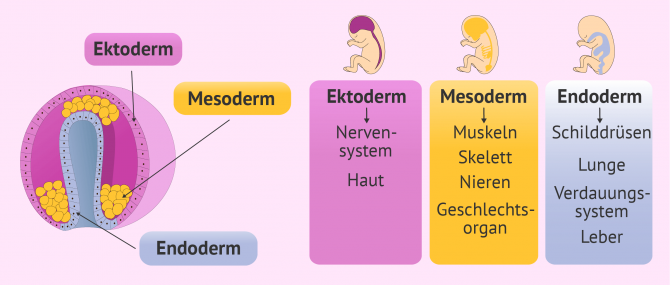

Nach der Einnistung in die Gebärmutterschleimhaut der Gebärmutter beginnt der Embryo sich zu entwickeln. Dieser Prozess ist als Gastrulation bekannt. Dieser besteht aus der Bildung der drei primordialen embryonalen Schichten, aus denen alle Organe und Gewebe des zukünftigen Babys entstehen.

Diese 3 embryonalen Schichten, die die trilaminare Keimscheibe bilden, sind die folgenden:

- Ektoderm

- ist die äußerste Schicht des Embryos und stammt aus den Epiblasten. Diese entwickelt die verschiedenen Gewebe und Organe wie das Nervensystem und die Haut.

- Mesoderm

- ist die äußerste Schicht des Embryos und stammt aus den Epiblasten. Sie sorgt unter anderem für die Entstehung von Muskeln, Knochen, dem Fortpflanzungssystem und des Kreislaufs.

- Endoderm

- ist die innere Schicht des Embryos. Sie entsteht aus dem Hypoblasten und einigen Zellen, die aus dem Epiblasten wandern. Sie schafft das Verdauungssystem, die Atmungsorgane, Leber und die meisten inneren Organe.